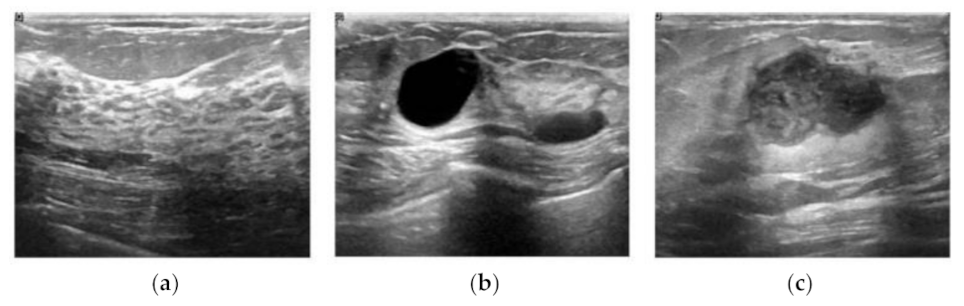

Although US imaging is one of the most popular modalities in practical clinical applications, it is difficult to find publicly available US image datasets in the literature. The dataset used in this study was recently released to the public, which consists of breast US images from 600 female patients aged between 25 and 75 years at the Baheya hospital in 2018 [15]. The data were acquired using the LOGIQ E9 ultrasound system and LOGIQ E9 Agile ultrasound system with the ML6-15-D matrix linear transducer, and converted gray scale images were obtained with an average size of 500 × 500 in PNG file format. The dataset consists of 780 B-mode images with pathological status and is categorized into three classes: normal, benign, and malignant. The numbers of images for the three classes are presented in Table 1, and the sample US images of each class are shown in Figure 1.

Figure 1. Sample B-mode images of the breast ultrasounddataset [11]; (a) Normal, (b) benign, and (c) malignant.